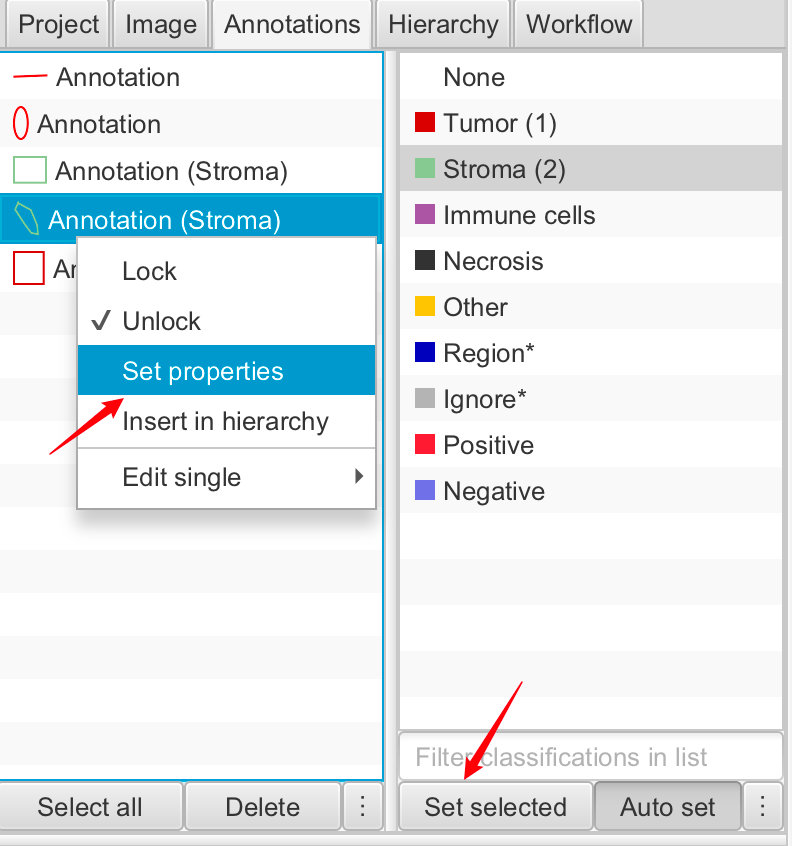

2-6:更改颜色和属性

现在返回分析面板(屏幕左侧),并点击注释标签。

您应该在这里看到您的注释列表。点击此列表是选择对象的一种方式。但如果您愿意,您也可以在这里设置注释的属性。

一种方法是选择右侧的预定义分类列表,并选择“Set class”。另一种方法是在列表中的任何注释上右键点击,然后选择“Set properties”以选择任意名称或颜色。

您可以使用N键来切换注释名称的可见性。

提示

您还可以通过选择注释并按Enter键来设置注释的属性。

3-2:锁定与解锁

注释可以是一项费力的过程。因此,丢失或意外编辑注释可能会相当令人沮丧。

为了帮助降低这种风险,注释可以被锁定或解锁。您可以通过右键点击选定的注释来访问这个功能。

3-3:设置属性

注释也可以设置属性。从分析的角度来看,这些属性中最重要的通常是分类。但从显示的角度来看,还有名称和颜色属性。

您可以通过按Enter键快速为选定的注释设置这些属性。

名称可以在查看器中显示或隐藏,使用“View ‣ Show names”,或快捷键N。